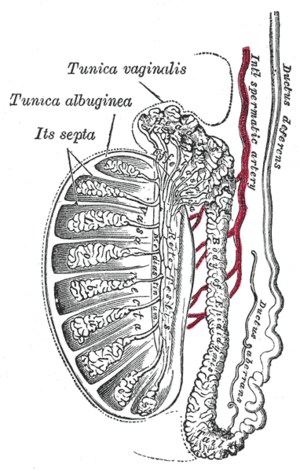

Vertical section of the testis, to show the arrangement of the ducts (internal spermatic artery labeled vertically at center) | |

Two or three of these accompany the ductus deferens, and supply the epididymis, anastomosing with the artery of the ductus deferens; others pierce the back part of the tunica albuginea, and supply the substance of the testis.